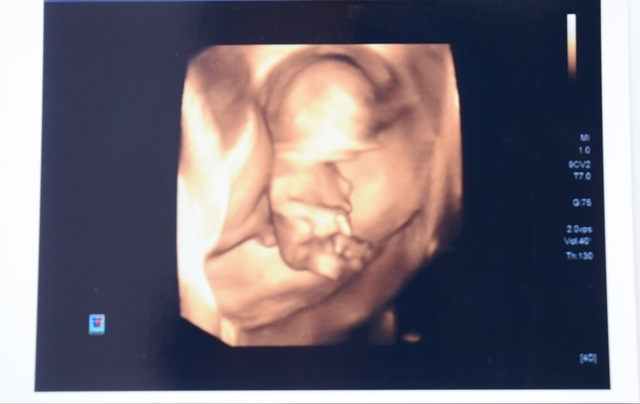

11週2日(11w2d・女の子)|ayane52 さん(19歳)

エコー写真撮影時のエピソード:

ハッキリと体全体が映っていてとても感動しました。 遅めのつわりが始まってとてもつらい時期でした。